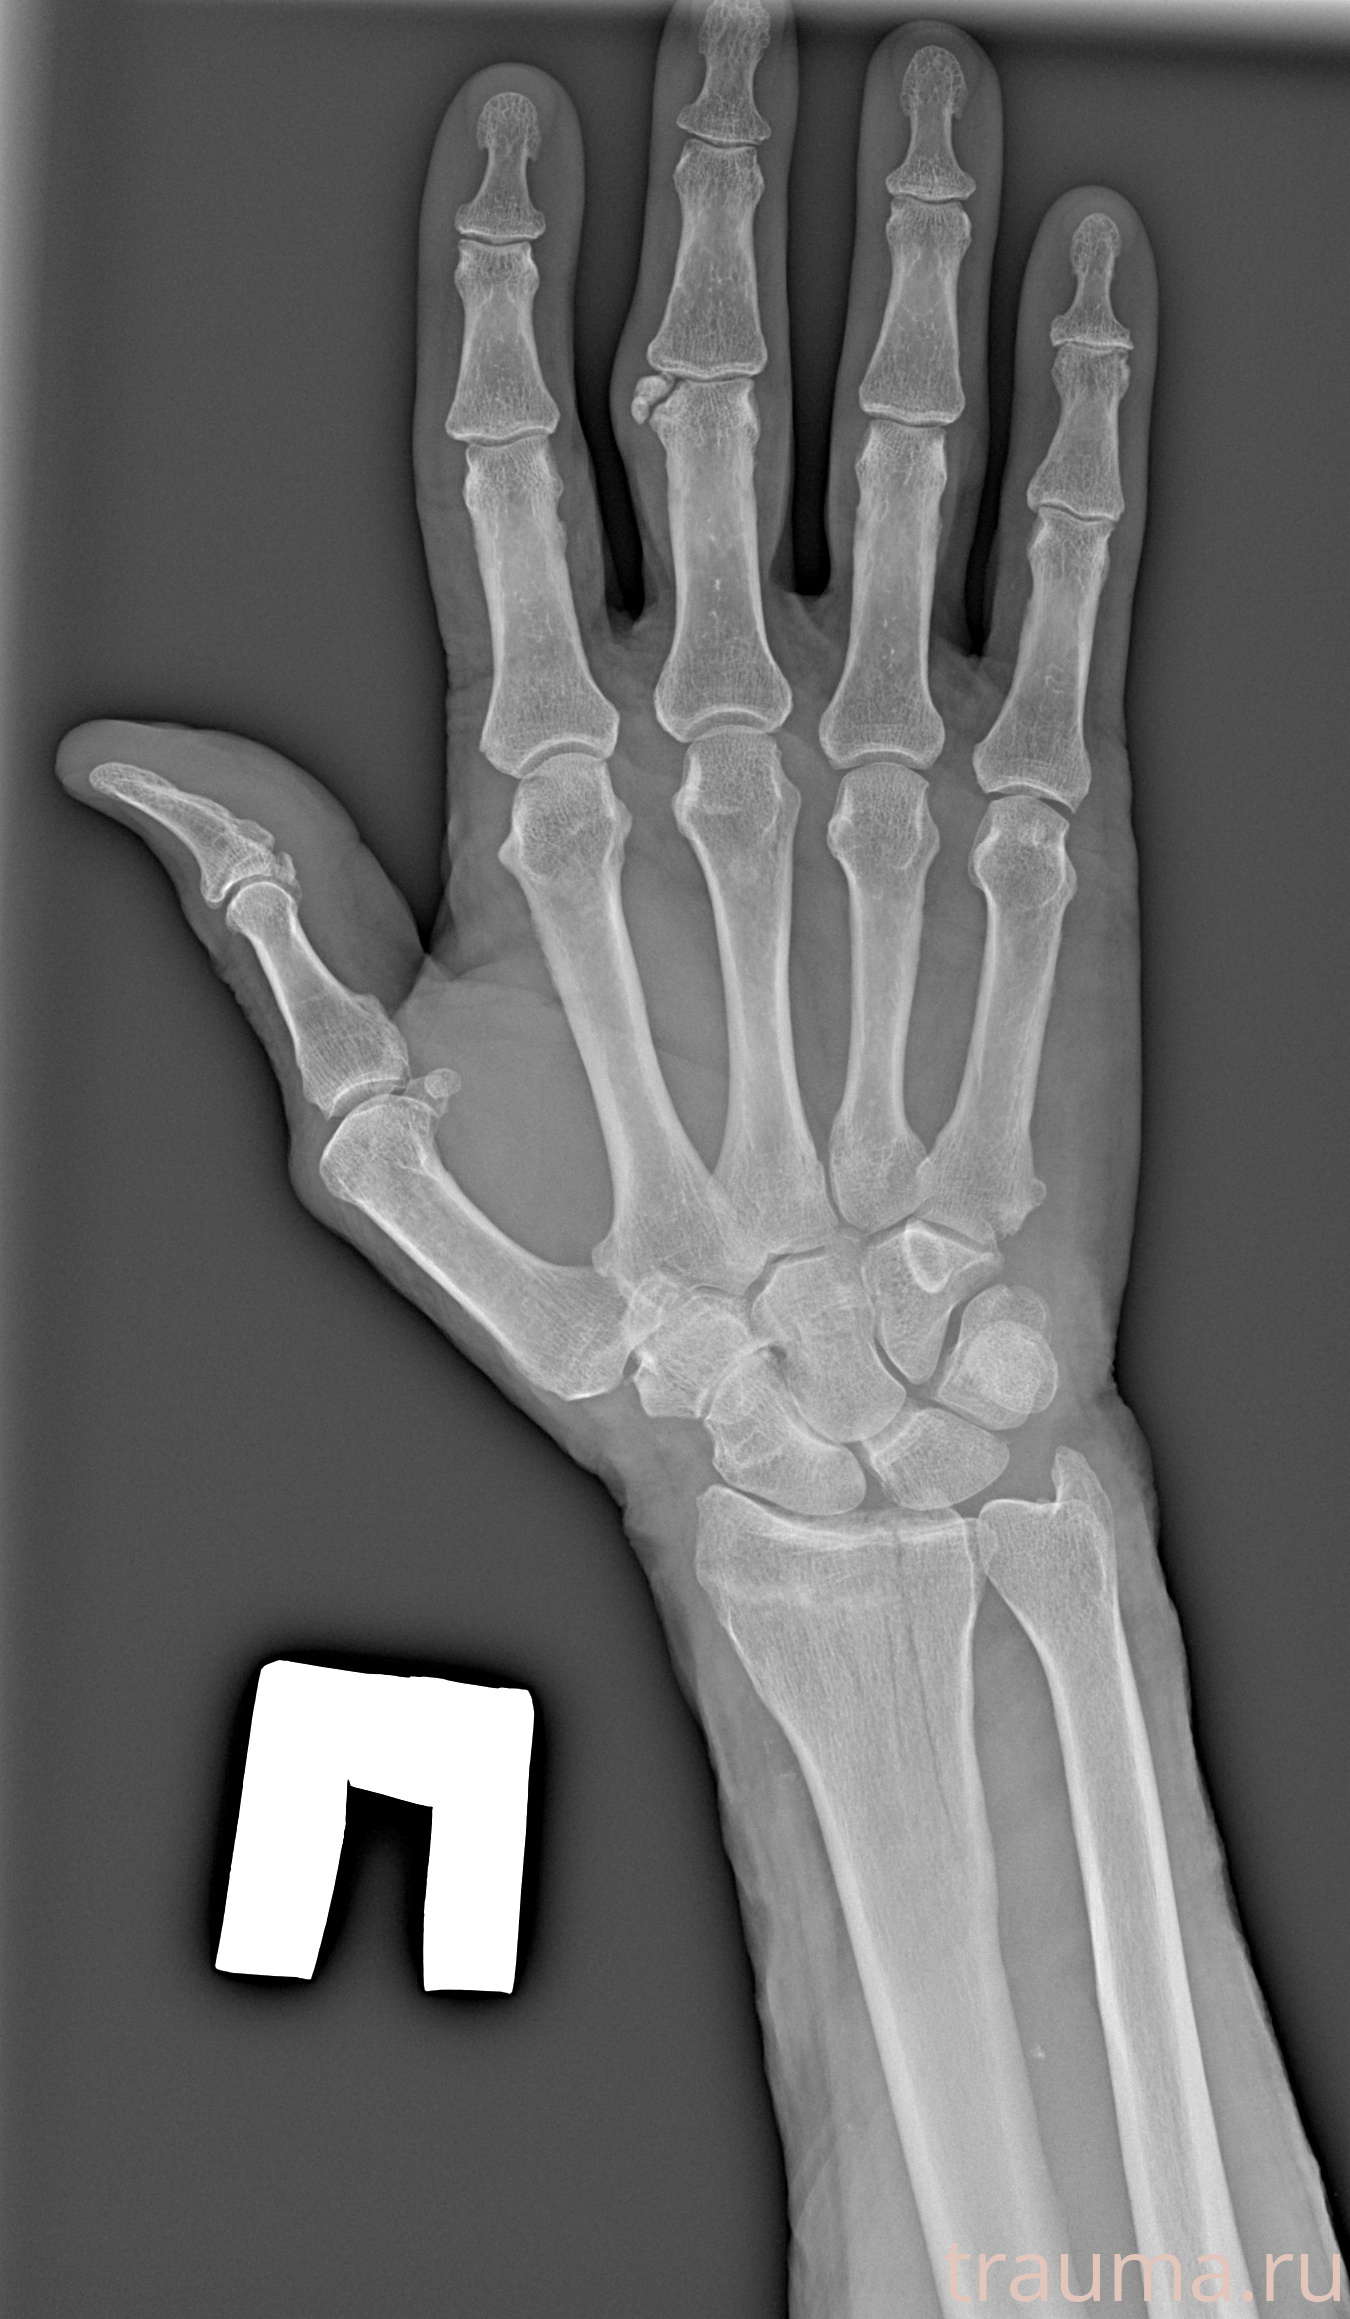

Рентгенограммы

Рентген на дому: по вашему адресу приезжает врач-рентгенолог, травматолог-ортопед с мобильным рентгеновским аппаратом, проводит диагностику травмы или заболевания, делает необходимые рентгенограммы, дает рекомендации по дальнейшему лечению. Получить качественные снимки в домашних условиях возможно благодаря уникальной методике, разработанной МосРентген Центром для института  Склифосовского